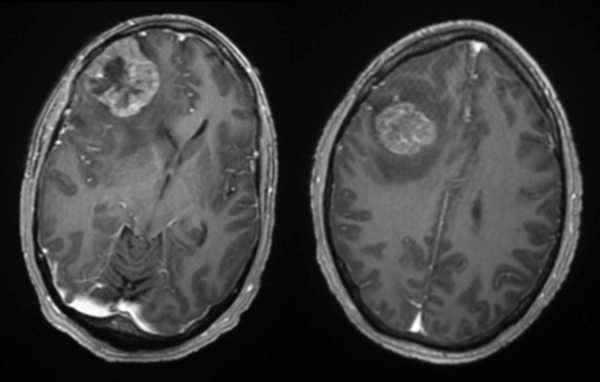

Post-op

Follow up imaging demonstrated a gross total resection for both intracranial metastases. The patient tolerated the surgery well and was discharged home on postoperative day four. At one-month follow-up, he was neurologically back to his baseline with a resolution of previous headaches and behavioral changes. He underwent postoperative stereotactic radiosurgery (Gamma Knife) to each surgical bed, followed by chemotherapy.